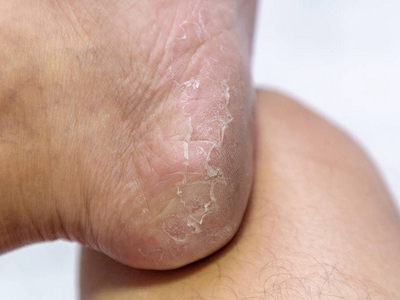

儿童期特应性皮炎发生于2岁以上的儿童,绝大多数由婴儿特应性皮炎延续发病,也有少部分儿童是在本期初发,多有丘疹、糜烂、苔藓样变等皮损表现。

儿童期特应性皮炎多呈现典型的湿疹改变,皮损渗出减少、干燥,以丘疹、糜烂和苔藓化为特点,特别好发于四肢、口周等处,最大特点是发生于两肘窝、两腘窝。皮损有轻度苔藓化,呈现糜烂面,少量渗出,自觉剧烈瘙痒。